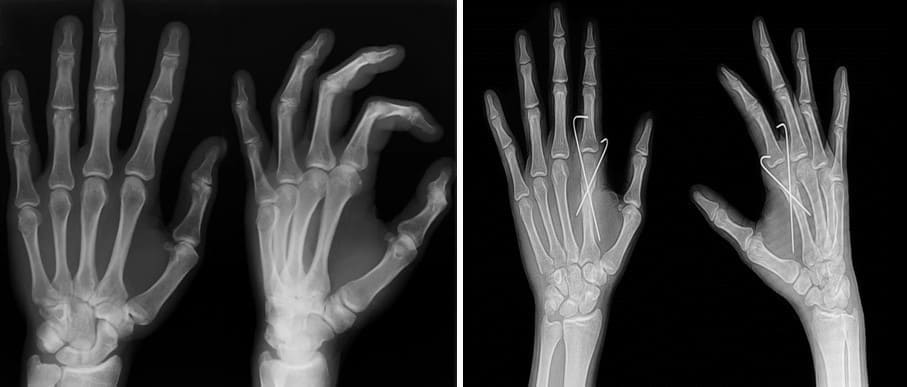

"¿Por qué arriesgarnos a perder piernas o manos en cirugías articulares que en el 98% de los casos se podrían evitar?"

En el proceso de curación las articulaciones se desgastan con los años. Esto puede llevar a la inmovilización total, a la discapacidad e incluso a la muerte. Cuando la situación se vuelve crítica, las personas son remitidas a nuestro centro para una operación. Esto implica riesgos y costes muy distintos. A veces no hay alternativa que no sea el reemplazo articular, que implica implantes. Sin embargo, los implantes son muy caros y no todos pueden pagarlos.

Con la edad desarrollé una grave artritis y osteoartritis. Las articulaciones de mis manos y dedos se deformaron, aparecieron protuberancias y mis rodillas sufrían un dolor terrible. La enfermedad me atormentó y me inmovilizó: no podía dormir ni moverme bien, y hasta bajar del transporte era un problema; en un momento me caí de un bus. Por miedo a convertirme en una carga para los míos, acudía con regularidad al médico, pero el dolor después de las cápsulas solo cedía momentáneamente. Podría haber aceptado una operación, pero tengo 70 años y no sabía cómo sería la recuperación. Por eso compré Arthrox. ¿Y saben qué? ¡El dolor desapareció! Los dolores articulares remitieron, la gota desapareció, las rodillas vuelven a doblarse, puedo moverme con libertad y me siento segura.

Amigos, ¡es un milagro! Los médicos me dijeron que lo único que podía hacer era aplicar ungüento en mis manos artríticas y tomar analgésicos. También me dijeron que la enfermedad no tiene cura. Arthrox me permitió recuperar mi forma. A los 60 años estoy al mismo nivel que mi sobrino, ¡es maravilloso! ¡Gracias, doctor!